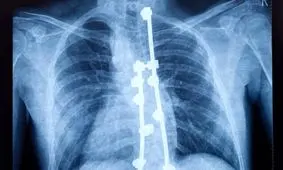

فناوری جدیدی که تصاویر HD از نخاع را در لحظه در اختیار جراحان قرار میدهد، میتواند به درمان دقیقتر کمردرد مزمن کمک کند.